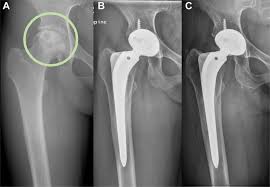

- 부분 치환술(Core Decompression 등): 골수 괴사 초기에 시행되며, 병변 부위만 최소 침습적으로 치료합니다.

- 정기 검진: 엑스레이 또는 CT로 인공관절의 상태 확인